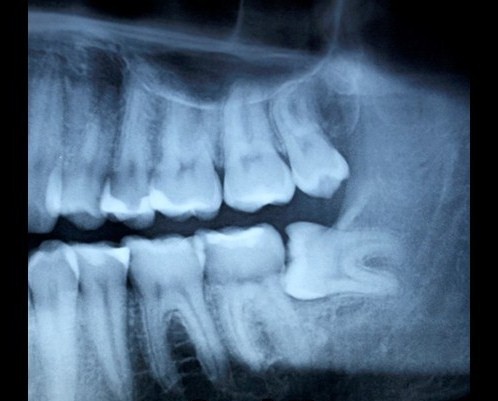

• You must attend an initial appointment where a complete medical history will be taken and the necessary additional tests (generally radiological: panoramic X-ray and dental CBCT) will be performed.